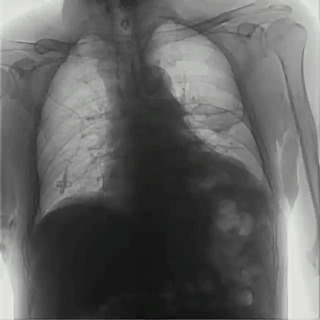

04百微平板,高清成像

普利德多功能動態(tài)DR采用100μm動態(tài)平板探測器,實現(xiàn)5.0lp/mm超高分辨率成像,大幅提升細節(jié)檢測能力;動態(tài)檢查幀率高達30幀/秒,有效避免漏診、誤診;靜態(tài)攝影有效像素高達1800萬,較之于傳統(tǒng)900萬點片像素,圖像細節(jié)更加清晰細膩,有助于醫(yī)生準確判斷病灶的位置、形態(tài)和大小,為急診救治提供可靠依據(jù)。